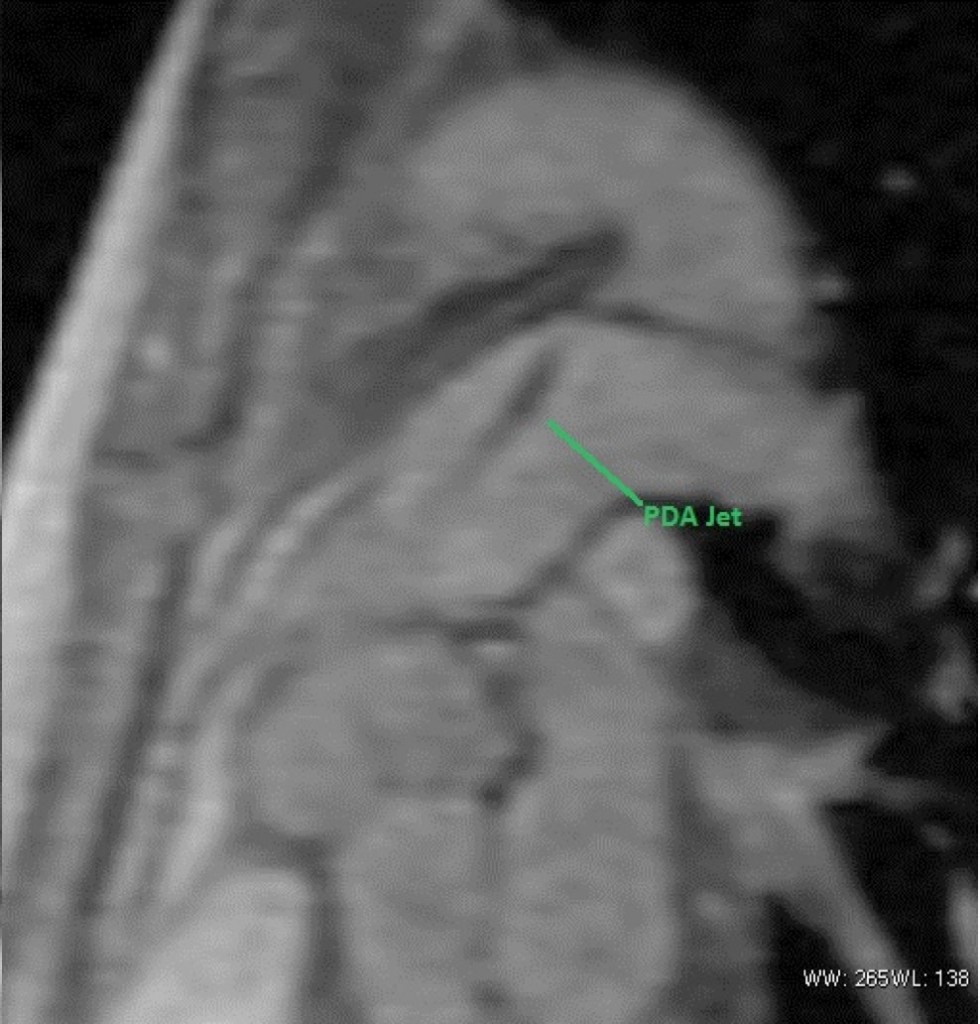

PDA or Patent Ductus Arteriosus Cardiac Case Studies CTisus CT Scanning

From www.ctisus.com

PDA or Patent Ductus Arteriosus Cardiac Case Studies CTisus CT Scanning Pda Heart Plug The amplatzer duct occluders are. The position of the device is. the device is made of a fine wire mesh, which plugs the flow of blood flow through the pda. — patent ductus arteriosus (pda) is a persistent opening between the two major blood vessels leading from the. The amplatzer™ duct occluder, duct occluder ii & piccolo™ occluder.. Pda Heart Plug.